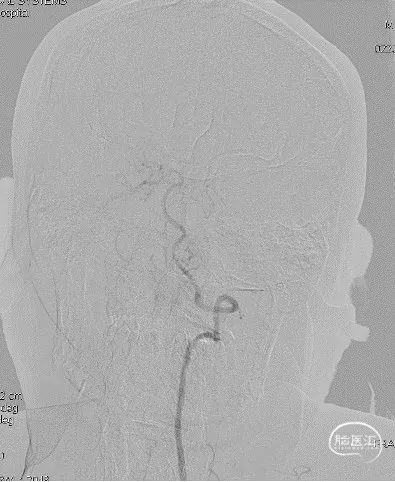

Sofia Plus导管有以下优点:

①柔顺性好、到位性能佳,能迅速通过虹吸段“C”或“U”形前膝甚至是“裸奔”到达病变部位,但使用时需务必注意近端给予足够支撑,头端预塑形可能有助于提高通过性;

②头段内径为目前同类产品最大,且抽吸操作时管腔不易变形,因此开通效率提高;

③可作为中间导管,一旦单纯抽吸不成功,可迅速转变手术策略。

栓塞原因所致的大血管急性闭塞(LVO),Sofia Plus直接抽吸取栓可作为优选开通方法。

Sofia Plus示意图